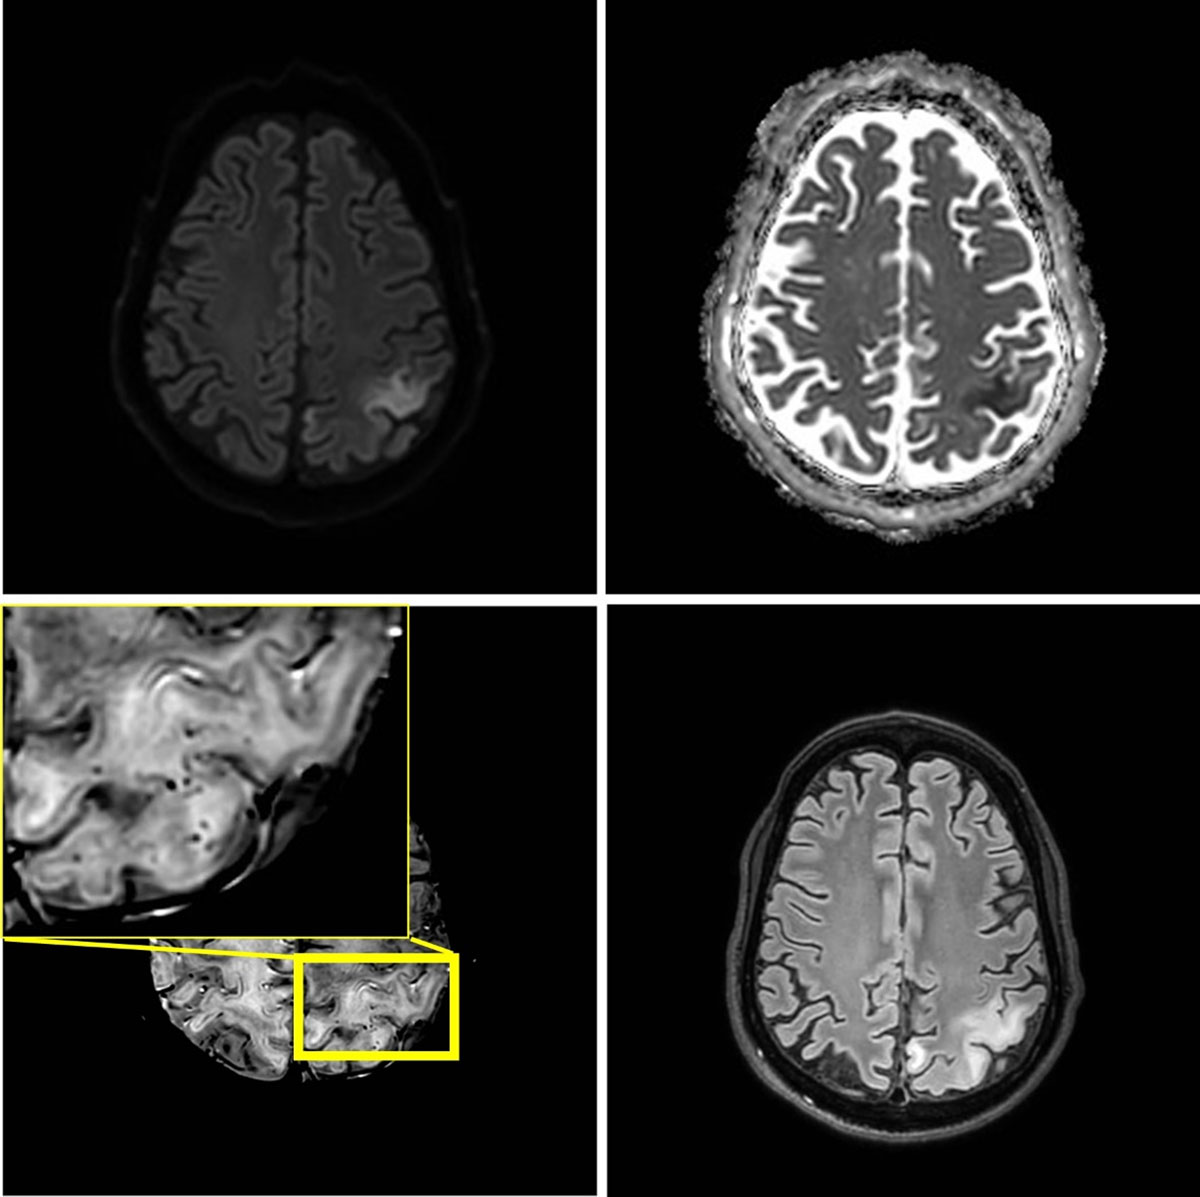

Figure 3

One month later, seven weeks after the initial episode, a third stroke-like event occurred. MRI shows a new area of edema in the left parietal lobe including the postcentral gyrus. The new lesion shows diffusion restriction and juxtacortical microhemorrhages.